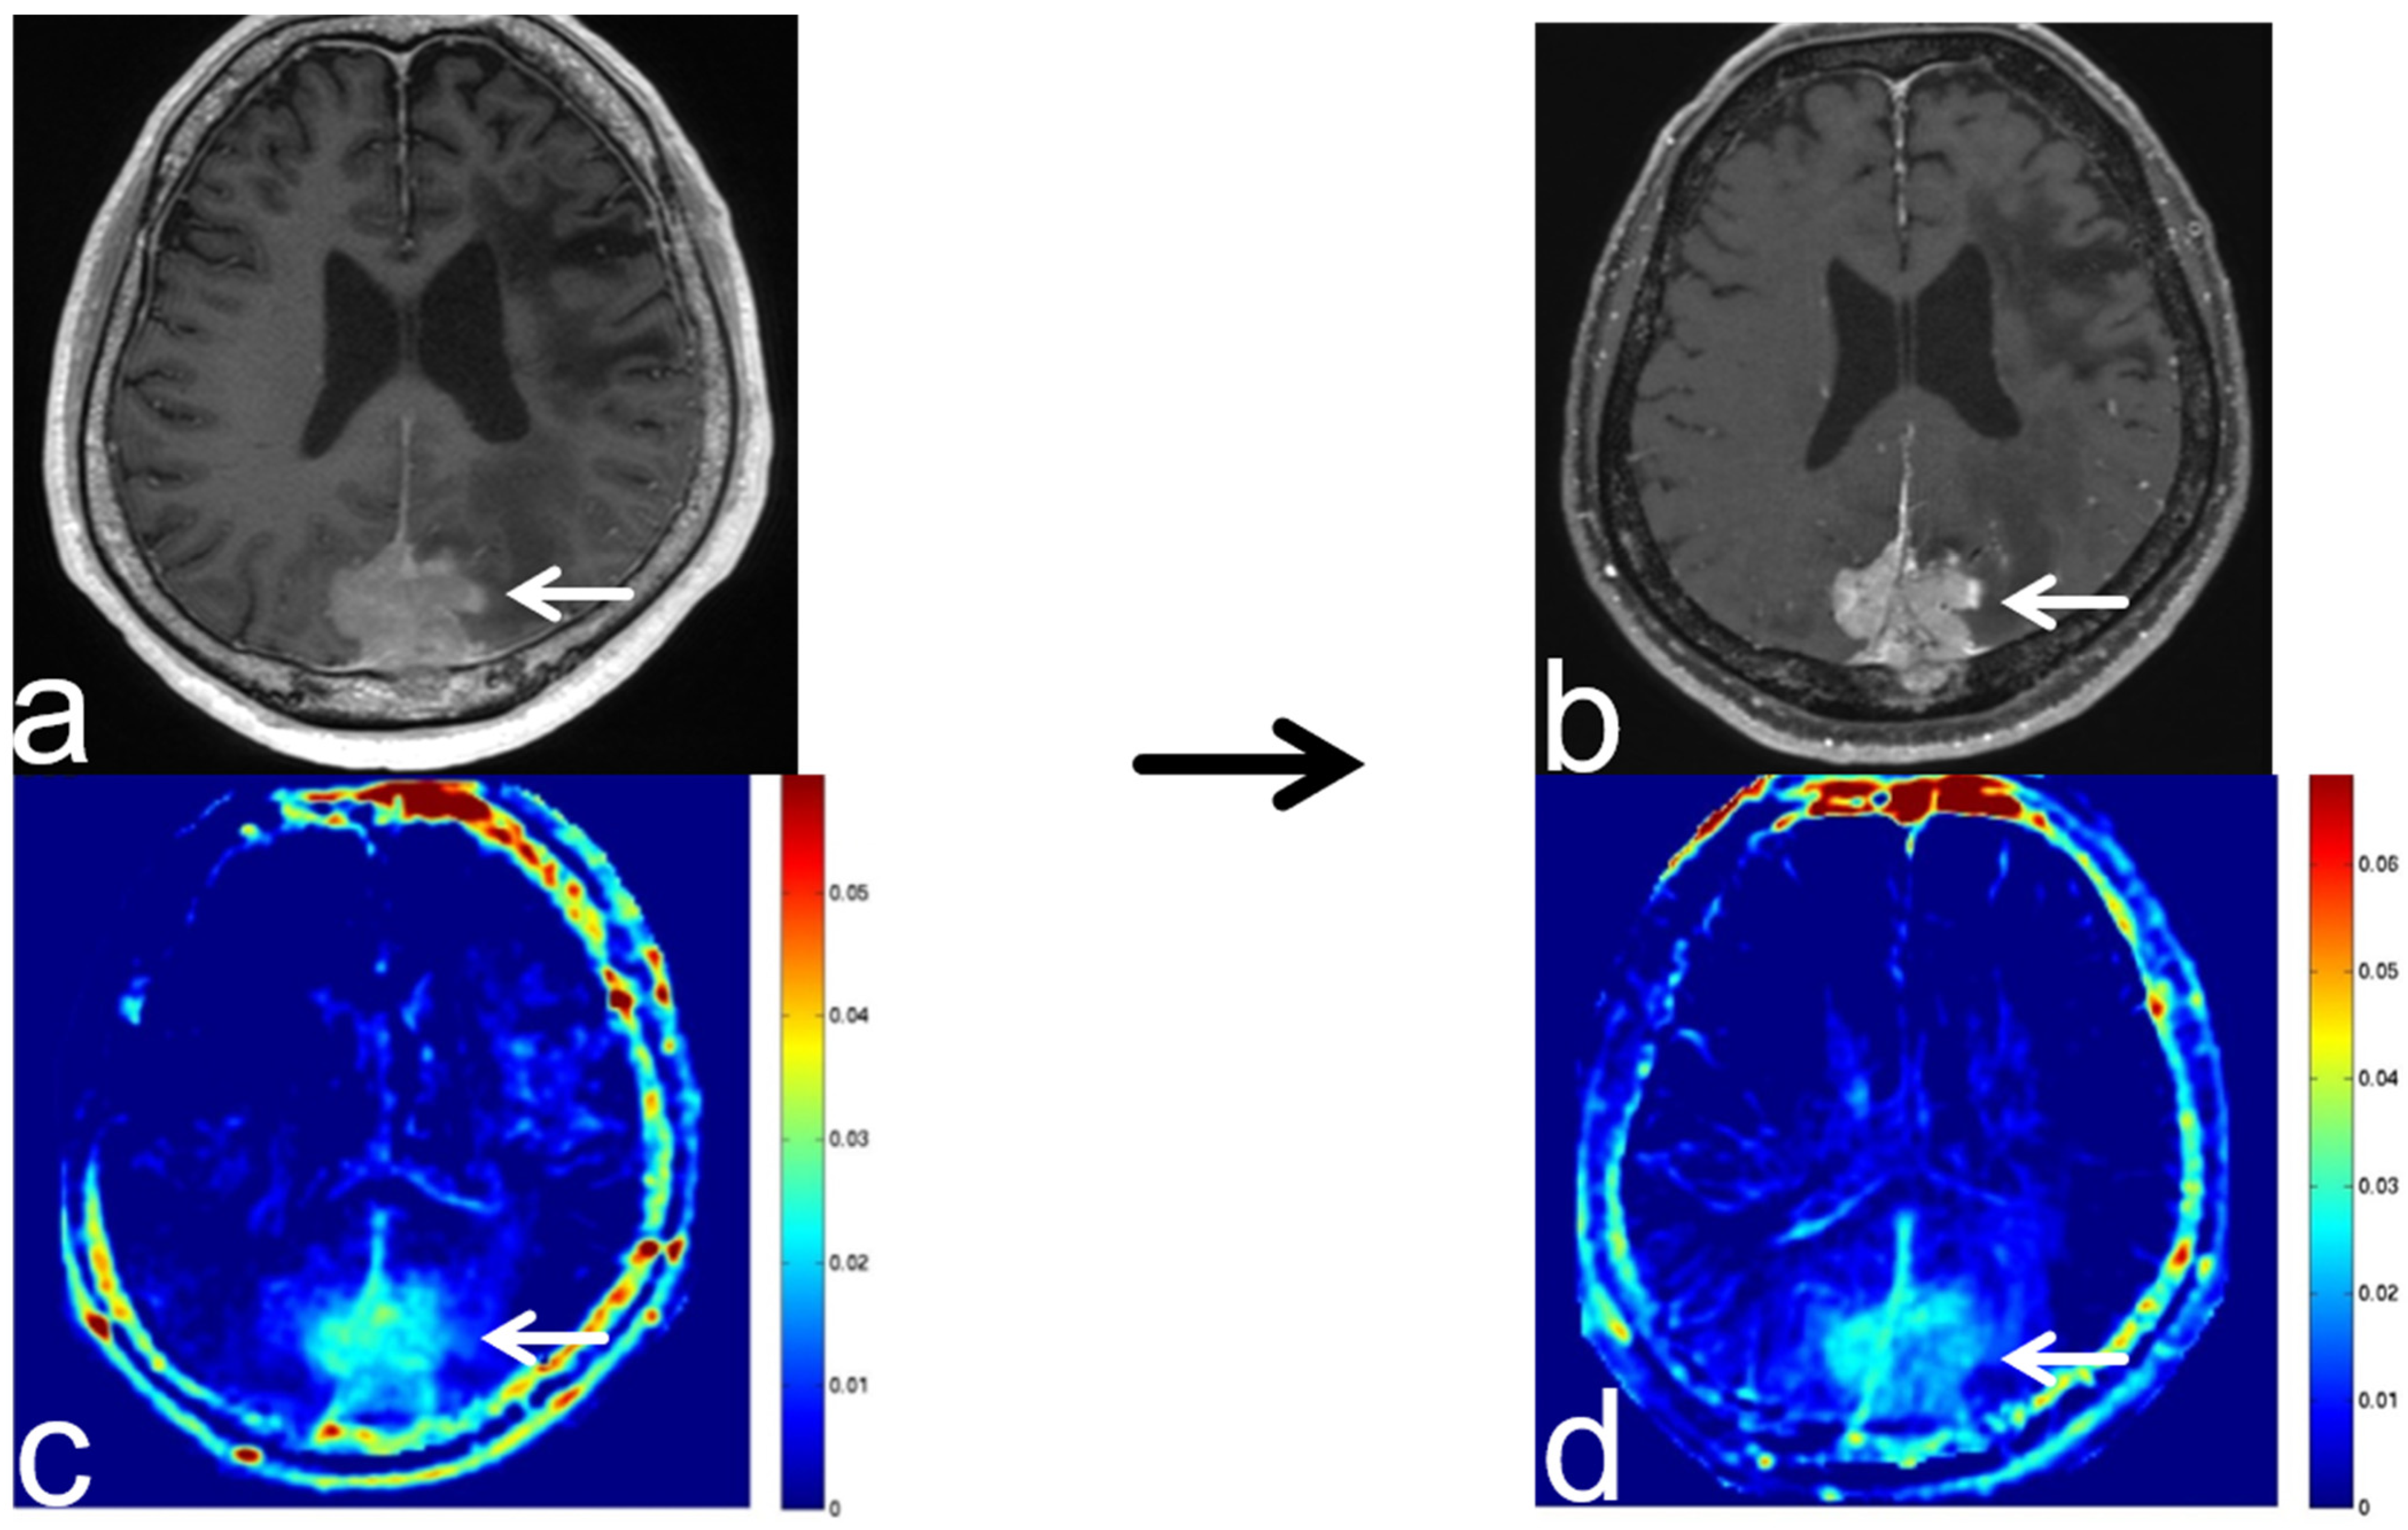

8.1. Radiation Necrosis